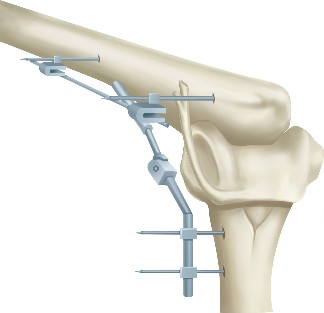

The correct answer is (A). Massive and immobile tears can be either U-shaped or longitudinal. These can sometimes be repaired using an anterior or posterior

interval slide technique. In an anterior interval slide technique, there is some anterior portion of the supraspinatus still attached to the greater tuberosity laterally and rotator interval anteriorly. The greater tuberosity attachment can be incised and the rotator interval attachment can be detached by incising the coracohumeral ligament. In a posterior interval slide technique, there is some posterior portion of the supraspinatus still attached to the infraspinatus. This can be detached by incising the interval between the supraspinatus and infraspinatus (Answer B). These interval slide techniques decrease the tension and improve lateral mobilization, allowing the supraspinatus to be more easily repaired to the greater tuberosity. The posterior leaf of the tear is then brought together with the anterior leaf through marginal convergence, leaving you with a small crescent-shaped tear that can be repaired to the greater tuberosity (see Fig. 2–16).

Figure 2–16_Massive, immobile rotator cuff tear and repair using anterior interval slide followed by marginal convergence. SS, supraspinatus; IS/TM, infraspinatus/teres minor; RI, rotator interval; CHL, coracohumeral ligament; Sub, subscapularis. (Redrawn from Burkhart SS, Lo IKY. Arthroscopic rotator cuff repair. J _Am Acad Orthop Surg. 2006;14(6):333–346.)